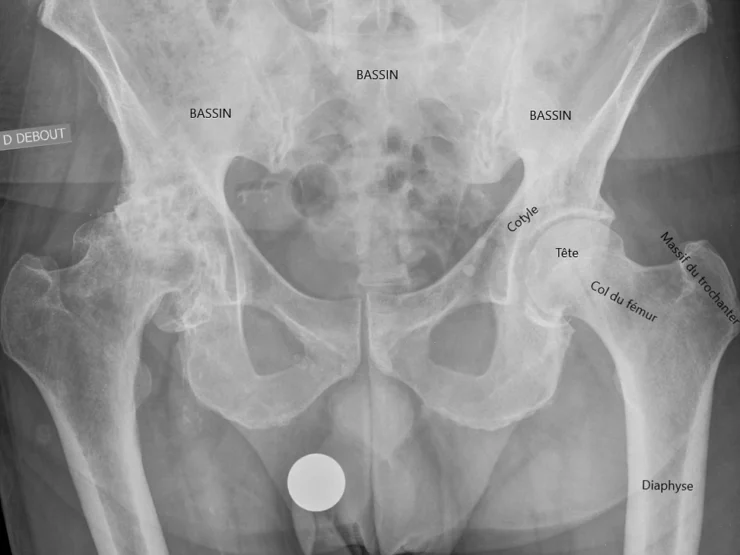

Le bassin est creusé d’une cavité arrondie appelée cotyle (ou acetabulum) dans laquelle s’articule l’extrémité supérieure sphérique du fémur appelée tête du fémur. Un joint appelé labrum, de consistance élastique assez ferme, coiffe le pourtour de la cavité et participe à la stabilité et la coaptation de l’articulation.

La hanche est aussi l’articulation la plus profonde du corps humain. Elle est enveloppée de plusieurs couches de muscles puissants qui, par l’intermédiaire de leur insertion tendineuse sur l’os, permettent le maintien en position debout, ainsi que les mouvements de flexion (vers l’avant), extension (vers l’arrière), abduction (écartement), adduction (rapprochement vers le coté opposé), rotation externe et interne.